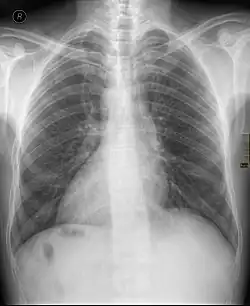

Dextrocardie

La dextrocardie est une malformation de naissance dans laquelle le cœur se trouve dans la moitié droite du thorax, l'hémithorax droit. La pointe du cœur est aussi orientée à droite.

Plus en détail, la dextrocardie peut être associée à une condition génétique plus largement handicapante, comme le syndrome de Marden-Walker, mais ce n'est pas le cas le plus fréquent. Il peut s'agir d'une particularité sans aucune conséquence pathologique ni nécessité d'intervention, le cœur ayant un aspect et un fonctionnement sains (situs inversus en miroir avec l'estomac à droite, le foie à gauche, notamment). La dextrocardie non syndromique (ou au sens strict)[1] peut cependant avoir des conséquences significatives quand elle s'associe à des malformations cardiaques (cardiopathie congénitale). Il s'agit ainsi d'une anomalie plus sérieuse quand l'estomac et le foie se situent quant à eux du côté ordinaire, ce qui est plus souvent associé à un organe mal formé et à de mauvaises connexions des vaisseaux sanguins. Il peut enfin s'agir de dextroposition du cœur, qui s'associe souvent à une cardiopathie congénitale, et résulte d'un déplacement en raison d'une malformation pulmonaire ou diaphragmatique[2]. La dextroposition et la dextroversion peuvent être considérées comme des pseudodextrocardies. La dextroversion est un cas très rare où les cavités cardiaques ne sont pas affectées par l'inversion[3].

L'anomalie peut être découverte lors d'un examen systématique, clinique ou radiologique, ou motivée par la présence d'autres malformations.